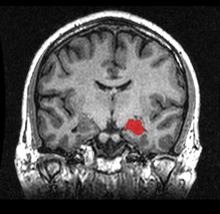

MRI coronal view of a hippocampus shown in red.

MRI coronal view of a hippocampus shown in red